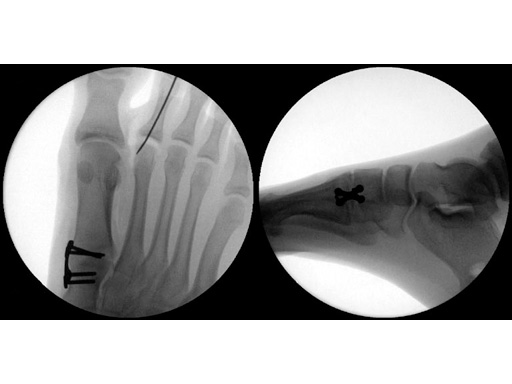

16-year-old male

Proximal first metatarsal growth-plate injury resulting in haluxvalgus. Arthrosis of first tarsometatarsal and second metatarsal hammer toe. Pain during activities and in general shoe wear.

Case provided by Carl Hasselman, Pennsylvania, USA

First MTP fusion and modified McBride with a distal soft-tissue release and second metatarsophalangeal (MTP) capsulotomy. A mini tight rope was used to hold and reduce the alignment of the first metatarsal. The X-plate was used to hold rigid fixation of the fusion. A K-wire was used for the second MTP capsulotomy.